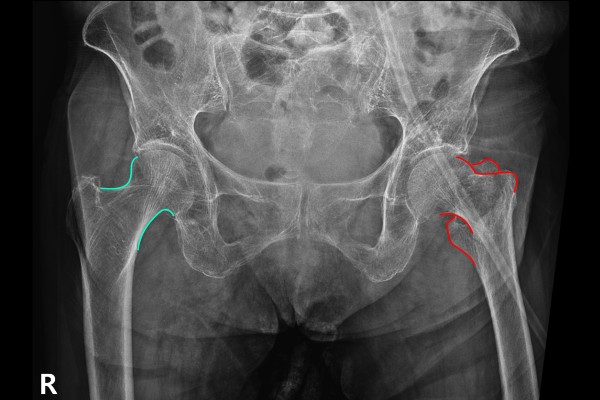

환자분의 정확한 상황을 파악하기 위해 먼저 X-RAY 촬영을 하였고, 촬영한 X-RAY에서 정상적인 우측 고관절목과 다르게 좌측 고관절목이 골절된 것이 확인됩니다.

측면에서 확인해보아도 고관절목이 부러져있는 것이 확인됩니다.